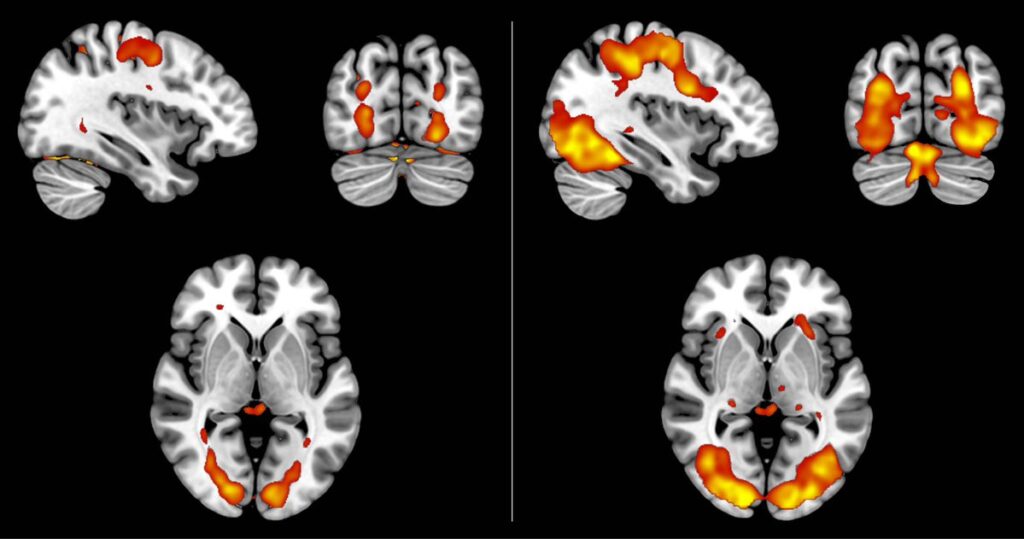

- Pianino bez dotykania klawiszy Neurobiolog Alvaro Pascual-Leone z Harvardu przeprowadził badanie, w którym jedna grupa osób ćwiczyła prosty utwór na pianinie fizycznie przez pięć dni. Druga grupa tylko siedziała i w myślach wyobrażała sobie granie – bez żadnego ruchu palców. Po pięciu dniach zmiany w korze ruchowej mózgu były niemal identyczne w obu grupach. Osoby, które jedynie wyobrażały sobie grę, poprawiły swoje umiejętności prawie tak samo jak te, które naprawdę ćwiczyły.